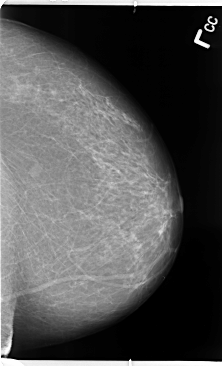

B_3113_1.LEFT_CC

LEFT_CC LINES 4752 PIXELS_PER_LINE 2880 BITS_PER_PIXEL 12 RESOLUTION 50 NON_OVERLAY